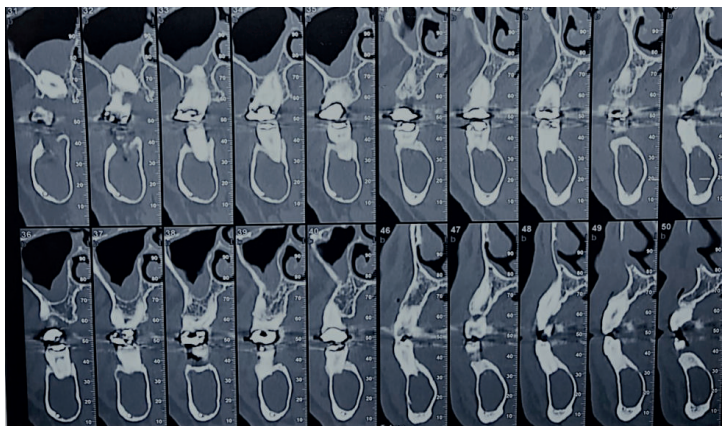

Acudió a servicio de cirugía oral, derivado por su odontólogo, un paciente varón de 65 años sin antecedentes médicos de interés, tras comprobar un importante crecimiento de una imagen radiotransparente respecto a última radiografía de hacía 5 años. El paciente no refirió sintomatología asociada. A la exploración extraoral no se apreció ningún tipo de deformidad ni afectación ganglionar. A la exploración intraoral pese a que se constató la integridad de las corticales, las cuales no estaban abombadas, sí que se pudo apreciar a la palpación un signo positivo de Dupuytren o de “Ping-Pong”. Además se constató una falta de afectación de los dientes del cuarto cuadrante que no presentaban movilidad y tenían una vitalidad positiva (Figura 1). Como complemento a la exploración clínica se solicitó un estudio mediante TAC, donde se apreció la extensión de una lesión radiotransparente que afectaba a rama y cuerpo mandibular derecho. (Figuras 2 y 3).

La cirugía se planteó bajo sedación y con el doble objetivo de la eliminación completa de la lesión con el cordal asociado y evitar un debilitamiento excesivo de la mandíbula. Para ello, se realizó un triple acceso a la lesión que nos permitiese por un lado despegar el quiste en toda su extensión mediante el uso de periostotomos y cucharillas de legrado, y por otro lado preservase una serie de “arbotantes” óseos que a su vez permitieran la posterior colocación de una mini placa desde la rama mandibular hasta el cuerpo, que actuase como refuerzo estructural (Figura 4).

A nivel local, se anestesiaron los nervios alveolar inferior y bucal mediante articaina 40mg/ml con 0.01 mg/ml de epinefrina (Ultracain® , España). Se realizó una incisión intrasulcular a espesor total con una descarga distal alta en la rama mandibular que se extendió hasta distal del canino inferior izquierdo sin necesidad de realizar una descarga en este punto. Se despegó el colgajo con la ayuda de un periostotomo para poder acceder a la superficie ósea. Con pieza de mano y fresa redonda de carburo de tugsteno se realizaron tres cavidades equidistantes: la primera a la altura del trígono retromolar (Figura 5), la segunda apical a los premolares inferiores derechos y la tercera mesio-apical al canino inferior derecho. Dichos accesos permitieron abordar y despegar toda la lesión en su extensión para posteriormente poder traccionar de ella a través de la cavidad media (Figuras 6 y 7). La cavidad posterior sirvió también para realizar la exodoncia del cordal (Figura 8). Tras la eliminación del quiste se llevó a cabo un legrado minucioso de la cavidad remanente y se limpió con agua oxigenada. A continuación, se colocó la mini placa con una extensión desde la rama mandibular hasta mesial de la cavidad media. Por último, se reposicionó el colgajo y se suturó de forma hermética mediante una sutura poliamida recubierta no reabsorbible de 4/0 Supramid (Aragó® ) (Figura 9). La muestra obtenida se conservó en formaldehido al 10% y se envió al anatomopatólogo, el cual confirmó el diagnóstico de quiste dentígero sin displasia celular (Figuras 10 y 11).